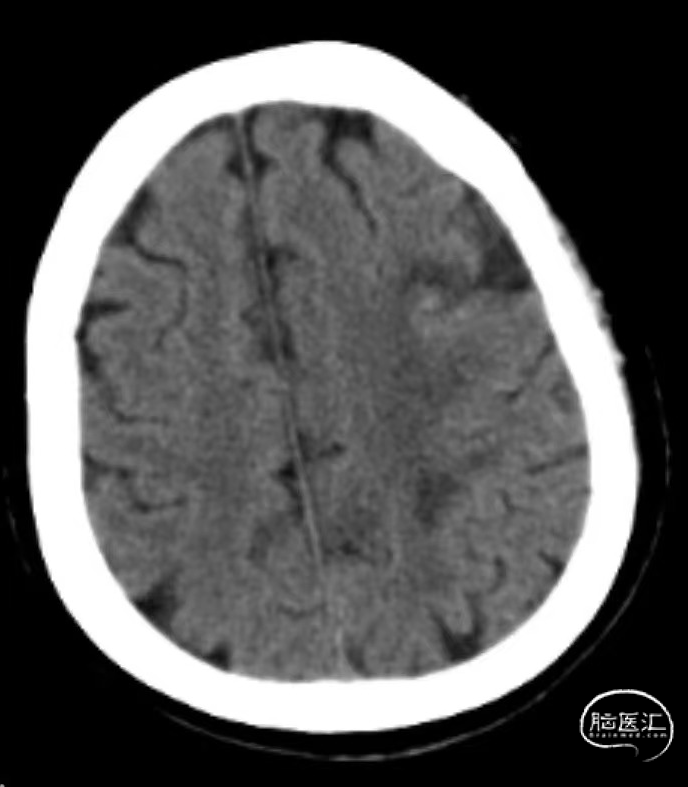

➤术后造影

➤术后CT

术后第二天复查头颅CT:无明显新发脑梗死。NIHSS评分7分(右上肢运动3分,右下肢运动2分,感觉1分,语言1分)。